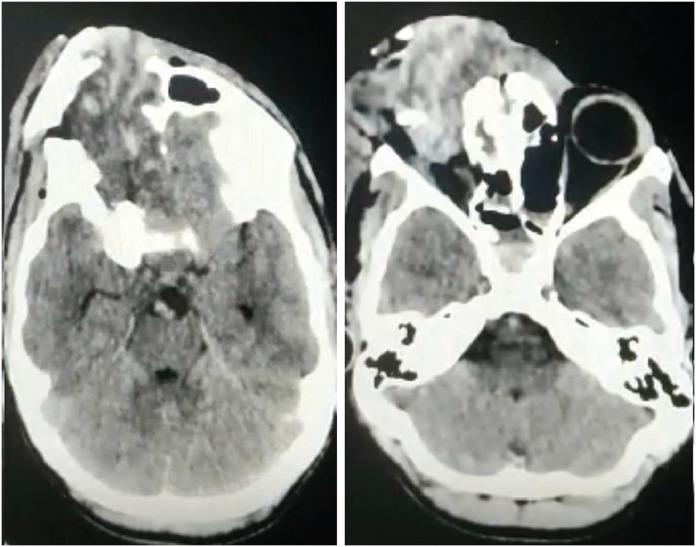

Farm-related head injuries are a significant cause of death and disability in rural households. Traumatic brain injury can result in long-term disability. The use of modern farming equipment has increased in the Indian agricultural sector over the last few decades. Machines such as threshers and winnowing devices can cause open skull fractures or scalp avulsions, while the fall of heavy tools may lead to severe head trauma. Farm animals such as bullocks and horses can also inflict traumatic brain injuries with their pointed horns, through trampling, kicking, or rarely biting. We present a case series of four patients who sustained head injuries due to farm-related accidents. All patients sustained compound cranial fractures with underlying brain parenchymal injuries, and three of them achieved complete recovery following timely medical intervention.

与农场相关的头部损伤是农村家庭死亡和残疾的一个重要原因。创伤性脑损伤可导致长期残疾。在过去几十年里,印度农业部门现代农用设备的使用有所增加。脱粒机和扬谷设备等机器可导致开放性颅骨骨折或头皮撕脱伤,而重型工具掉落可能导致严重的头部创伤。公牛和马等农场动物也可能用它们的尖角、通过踩踏、踢踹或极少情况下的撕咬造成创伤性脑损伤。我们报告了一系列4例因与农场相关的事故而头部受伤的患者。所有患者均发生复合性颅骨骨折并伴有潜在的脑实质损伤,其中3例经及时医疗干预后完全康复。